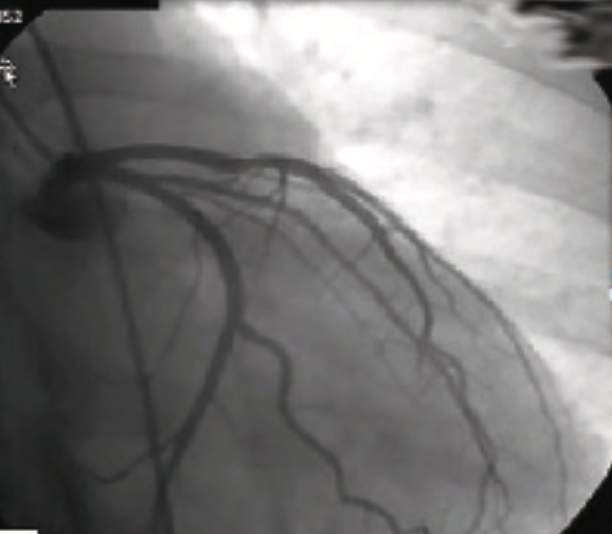

Abstract. Myocardial infarction has been reported as a rare manifestation of protein S deficiency. We describe the case of a 38-year-old woman with no traditional cardiovascular risk factors, presenting with myocardial infarction after a recent previous misdiagnosis of a non-ST elevation myocardial infarction as acute myocarditis. Coronary angiography revealed a thrombotic lesion in the proximal segment of the left anterior descending artery, successfully treated with coronary angioplasty. The laboratory test identified a protein S deficiency, and the appropriate treatment with oral anticoagulation was initiated.